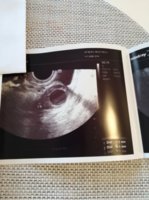

Siinä se mun munasolu ois XD jotenkin huvittavaa :angelic:

Muoks. Gyne siis kirjannut näin:

Endometrium tasainen kaunis triple layer 8,8mm. Molemmat ovariot kooltaan ja rakenteeltaan norm. Näköiset. Oikea ovario 37x30 mm, siinä komea simplex rakkula 21mm,sopisi preovulatoriseksi follikkeliksikin.

Lupaavat speksit :blob7